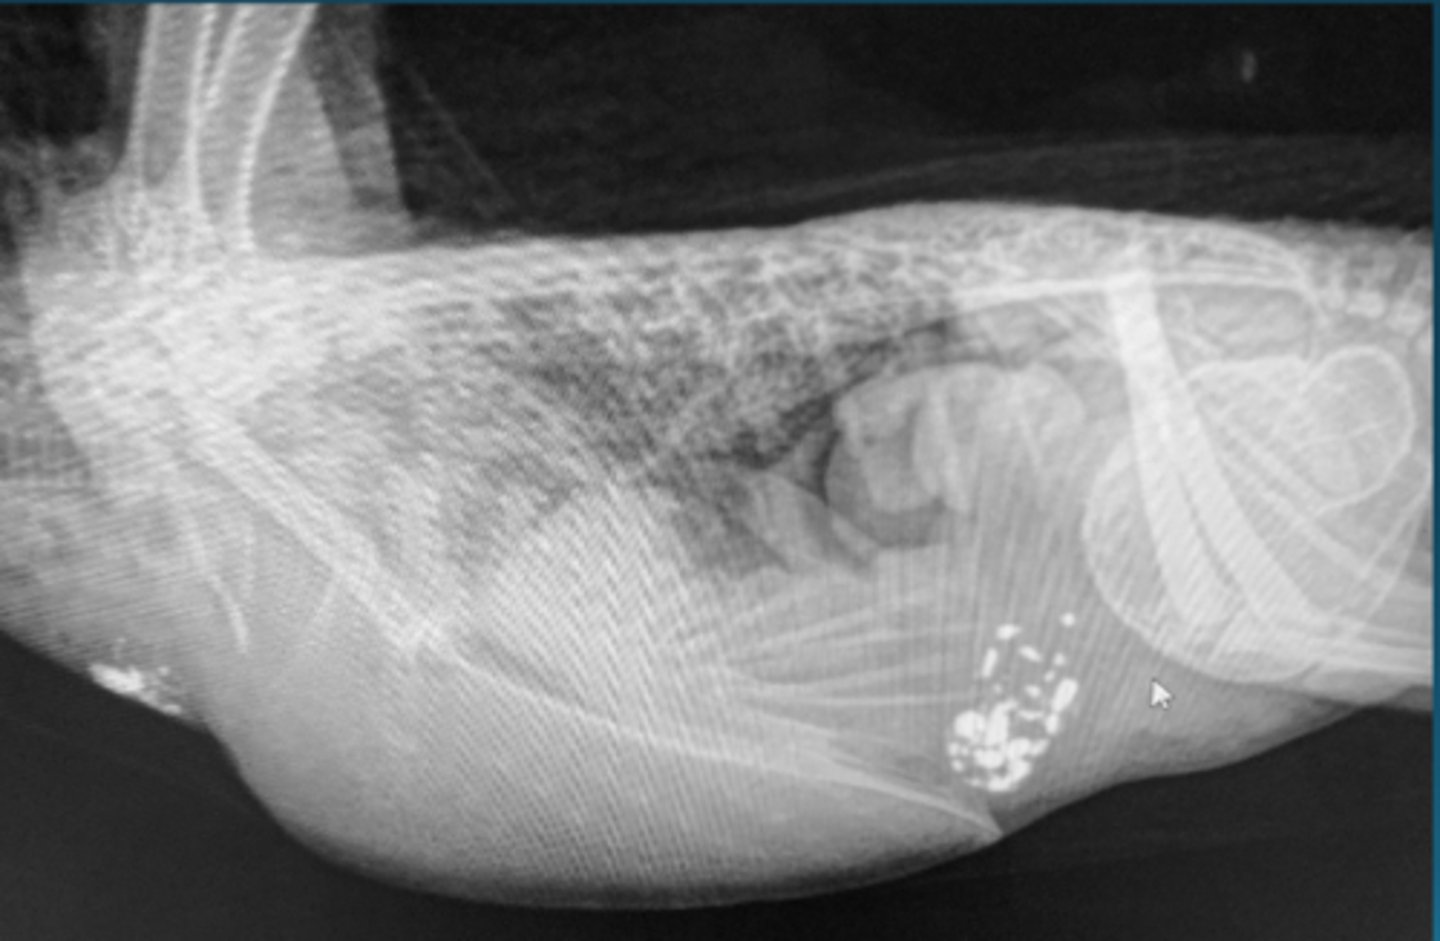

1. multiple soft tissue nodules located in the area of the kidney, these are ovarian follicles

2. there are abnormal tissue "spheres" where the air sacs should be with irregular "eggs" that will probably not come thru on their own

3. metal or mineral opacity in crop (esophagus diverticulum) and ventriculus (gizzard) causing dorsocaudal displacement of the mass above it

Describe some things you are seeing in this bird